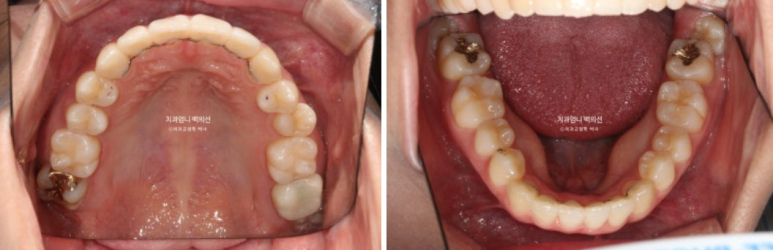

가지런한 앞니 배열과 철사 유지장치

24.09

부분교정인만큼 치근흡수는 없고 뿌리 평행도도 양호합니다.